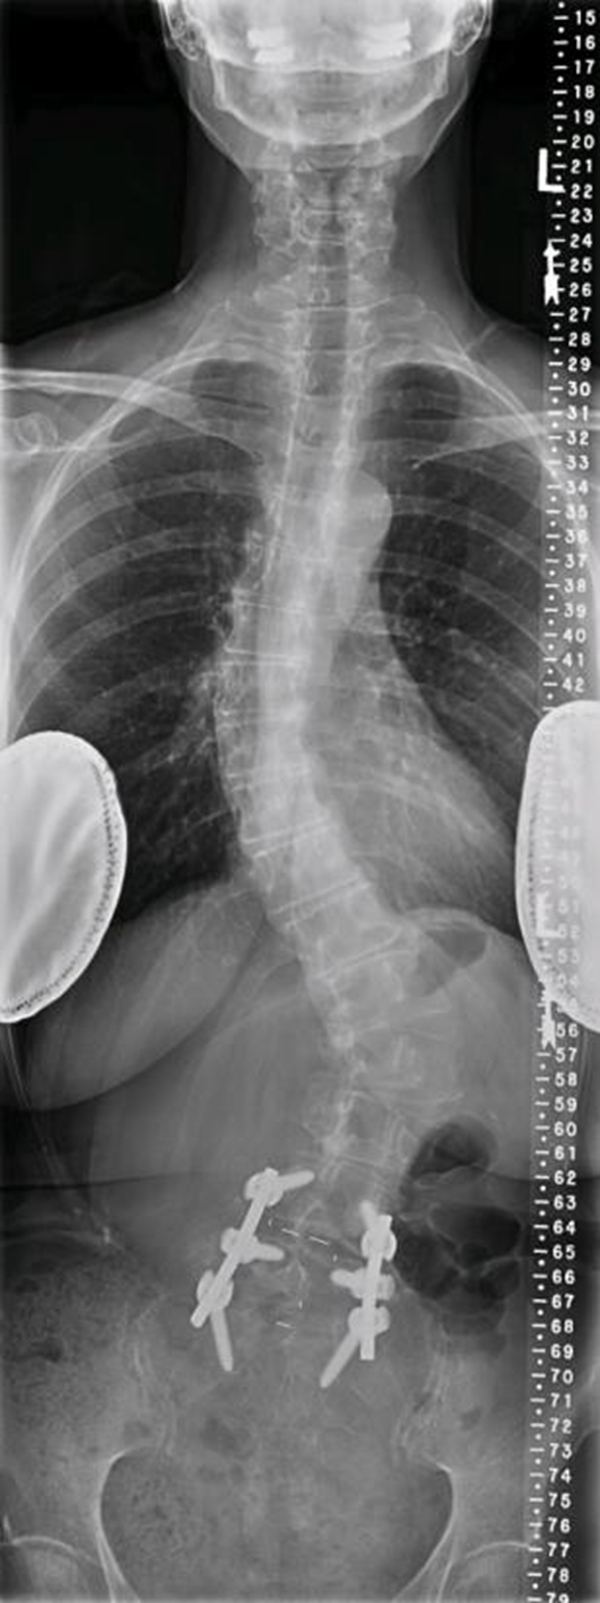

术前X线

术后X线